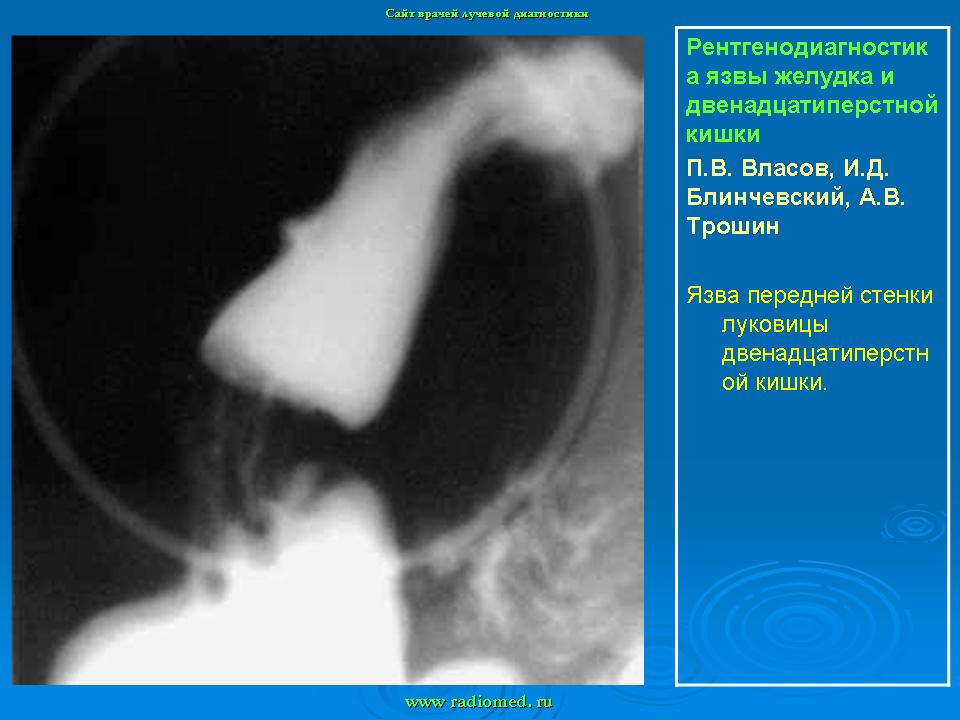

Пищеварительная система. Рентгенодиагностика язвы желудка и 12-ти перстной кишки. +

Рентгенодиагностика язвы желудка и 12-ти перстной кишки.

Данная статья помещена не только с познавательной целью, но и в дискуссионном плане.